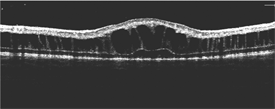

Figure 3.

An electroretinogram (ERG) test, which evaluates the electrical “circuitry” properties of the retina, shows a typical finding in patients with CXLRS (selective reduction of the amplitude of the b-wave). Optical coherence topography (OCT)—a way of imaging the retinal structure— demonstrates the typical intraretinal cystic spaces (Figure 3).